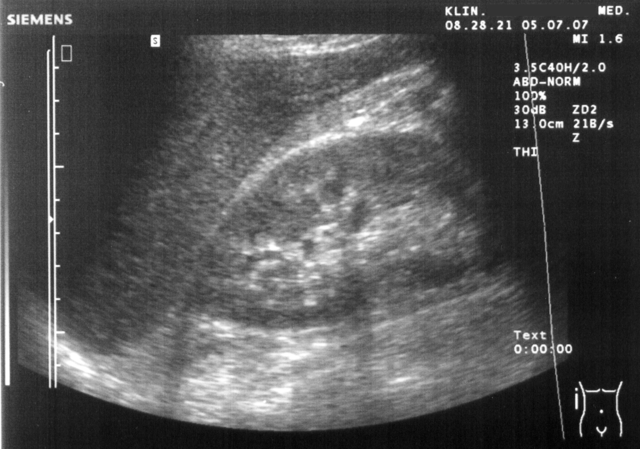

Dans la plupart des cas, l’échographie rénale et vésicale constitue l’examen d’imagerie de

première intention. Non invasive et facilement accessible, elle permet de visualiser les reins

et la vessie, et de détecter un obstacle, une masse ou une dilatation des voies urinaires.

Toutefois, son efficacité dépend du contexte clinique, et ses limites peuvent conduire à

prescrire un scanner ou une IRM en seconde intention.

L’échographie rénale et vésicale est généralement le premier examen prescrit face à une

hématurie. Elle est non invasive, sans irradiation, et offre une bonne visualisation des reins

et de la vessie. Elle permet de détecter des calculs, des masses rénales ou une rétention

urinaire. Toutefois, elle présente des limites, notamment pour évaluer les voies excrétrices

supérieures ou pour identifier des lésions urothéliales de petite taille.